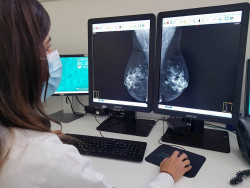

La tomosíntesis con mamografía sintética mejora la detección del cáncer de mama

La tomosíntesis digital de mama (TDM) en combinación con la mamografía sintética mejora la detección del cáncer sobre la mamografía digital sola, según un estudio de investigadores italianos publicado en la revista `Radiology`. Los resultados del estudio añaden más apoyo al uso de TDM en programas de detección de cáncer de mama basados en el cribado poblacional.